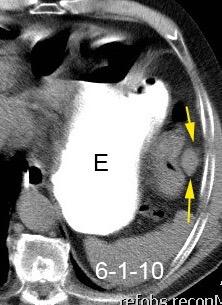

Aneurisma aórtico intracrural

/Restrepo CS et al. The diaphragmatic crura and retrocrural space: normal imaging appearance, variants, and pathologic conditions. Radiographics 2008